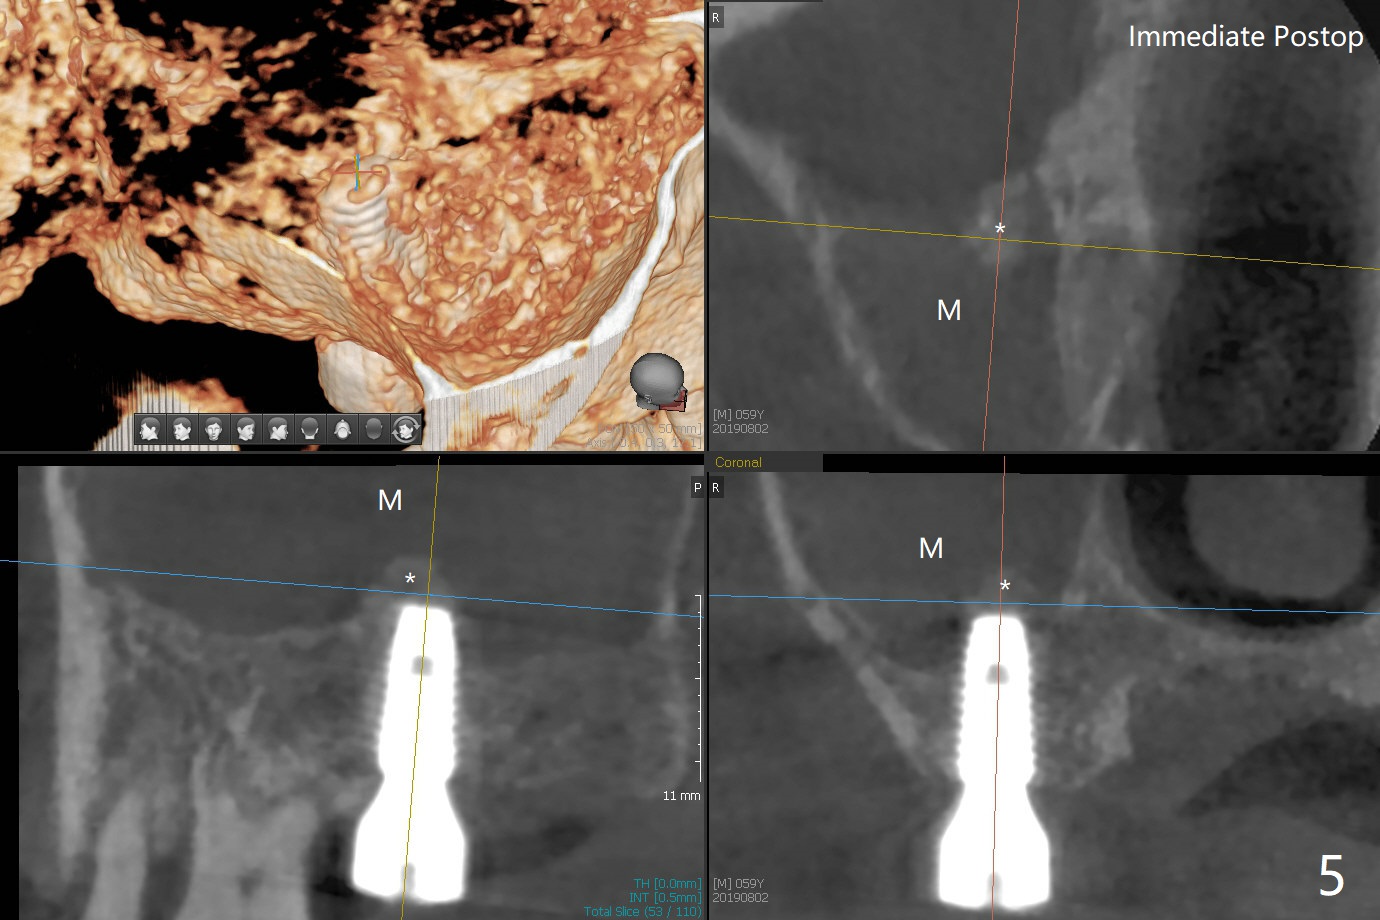

Two things happen immediately before this surgery. A SM implant is found to fail related to bruxism and poor oral hygiene, ~ 5 years in function; a UF implant will be used instead. DIO Sinus Approach Kit has not been autoclaved; therefore the free-hand one has to be used with caution. In fact the procedure goes on apparently smoothly in spite of the fact that the patient with medical knowledge is nervous about the risk of sinus lift. After 4.0x8.5 mm Neo Navi drill with 12 mm offset, the 3.6 mm sinus safety drill is used from 7 to 9 mm in length, followed by water balloon, PRF membranes (x2) and mixture of autogenous bone graft and allograft and 4.5x10 mm dummy implant (Fig.1). The definitive implant is placed with satisfactory stability (Fig.2), but a 6.5x7(4) mm healing abutment is close to the mesial crest (*). The former is reloaded following 6.0 mm Bone Profile Drill (Fig.3) and then is changed to a 6x6 mm IS one. The patient reports nasal hemorrhage immediately returning home, but there is no similar episode a few hours later. Re-analysis of preop (Fig.4) and immediate postop (Fig.5) CT shows that water balloon technique in fact swells the sinus membrane (M) instead elevating it. It is safe to place more bone graft (Fig.5 *). There is pain when the 6x6 mm healing abutment is being removed nearly 5 months postop (Fig.6.7). The patient complains of mild sinus discomfort, although panoramic X-ray does not show abnormality (Fig.8). He will return for recheck for implant stability (low bone density) before impression 2-4 months later.